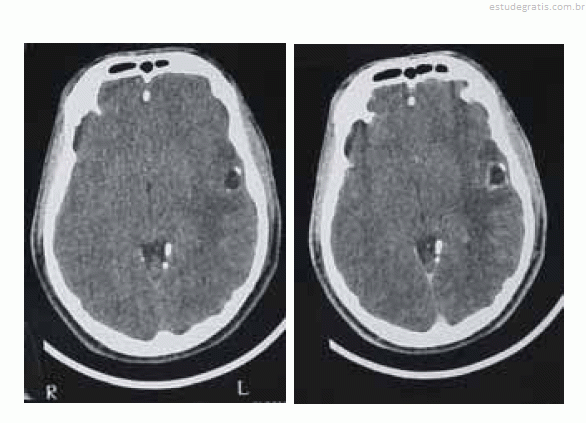

Uma paciente de 35 anos de idade foi levada ao prontosocorro após uma convulsão. Ao exame de admissão, encontravase confusa, sonolenta, porém reativa ao chamado. Apresentava sutil paresia braquiofacial direita. O esposo informou que, nos últimos cinco meses, a paciente começou a apresentar dificuldade para se comunicar, troca de palavras e dificuldade para nomeação. Há duas semanas, o quadro piorou e começou a ficar desligada e a apresentar abalos musculares no membro superior direito, de rápida duração, além de queixar-se de dor de cabeça. Foi realizada uma tomografia computadorizada (TC) de crânio, sem e com contraste, obtendo-se as imagens a seguir.